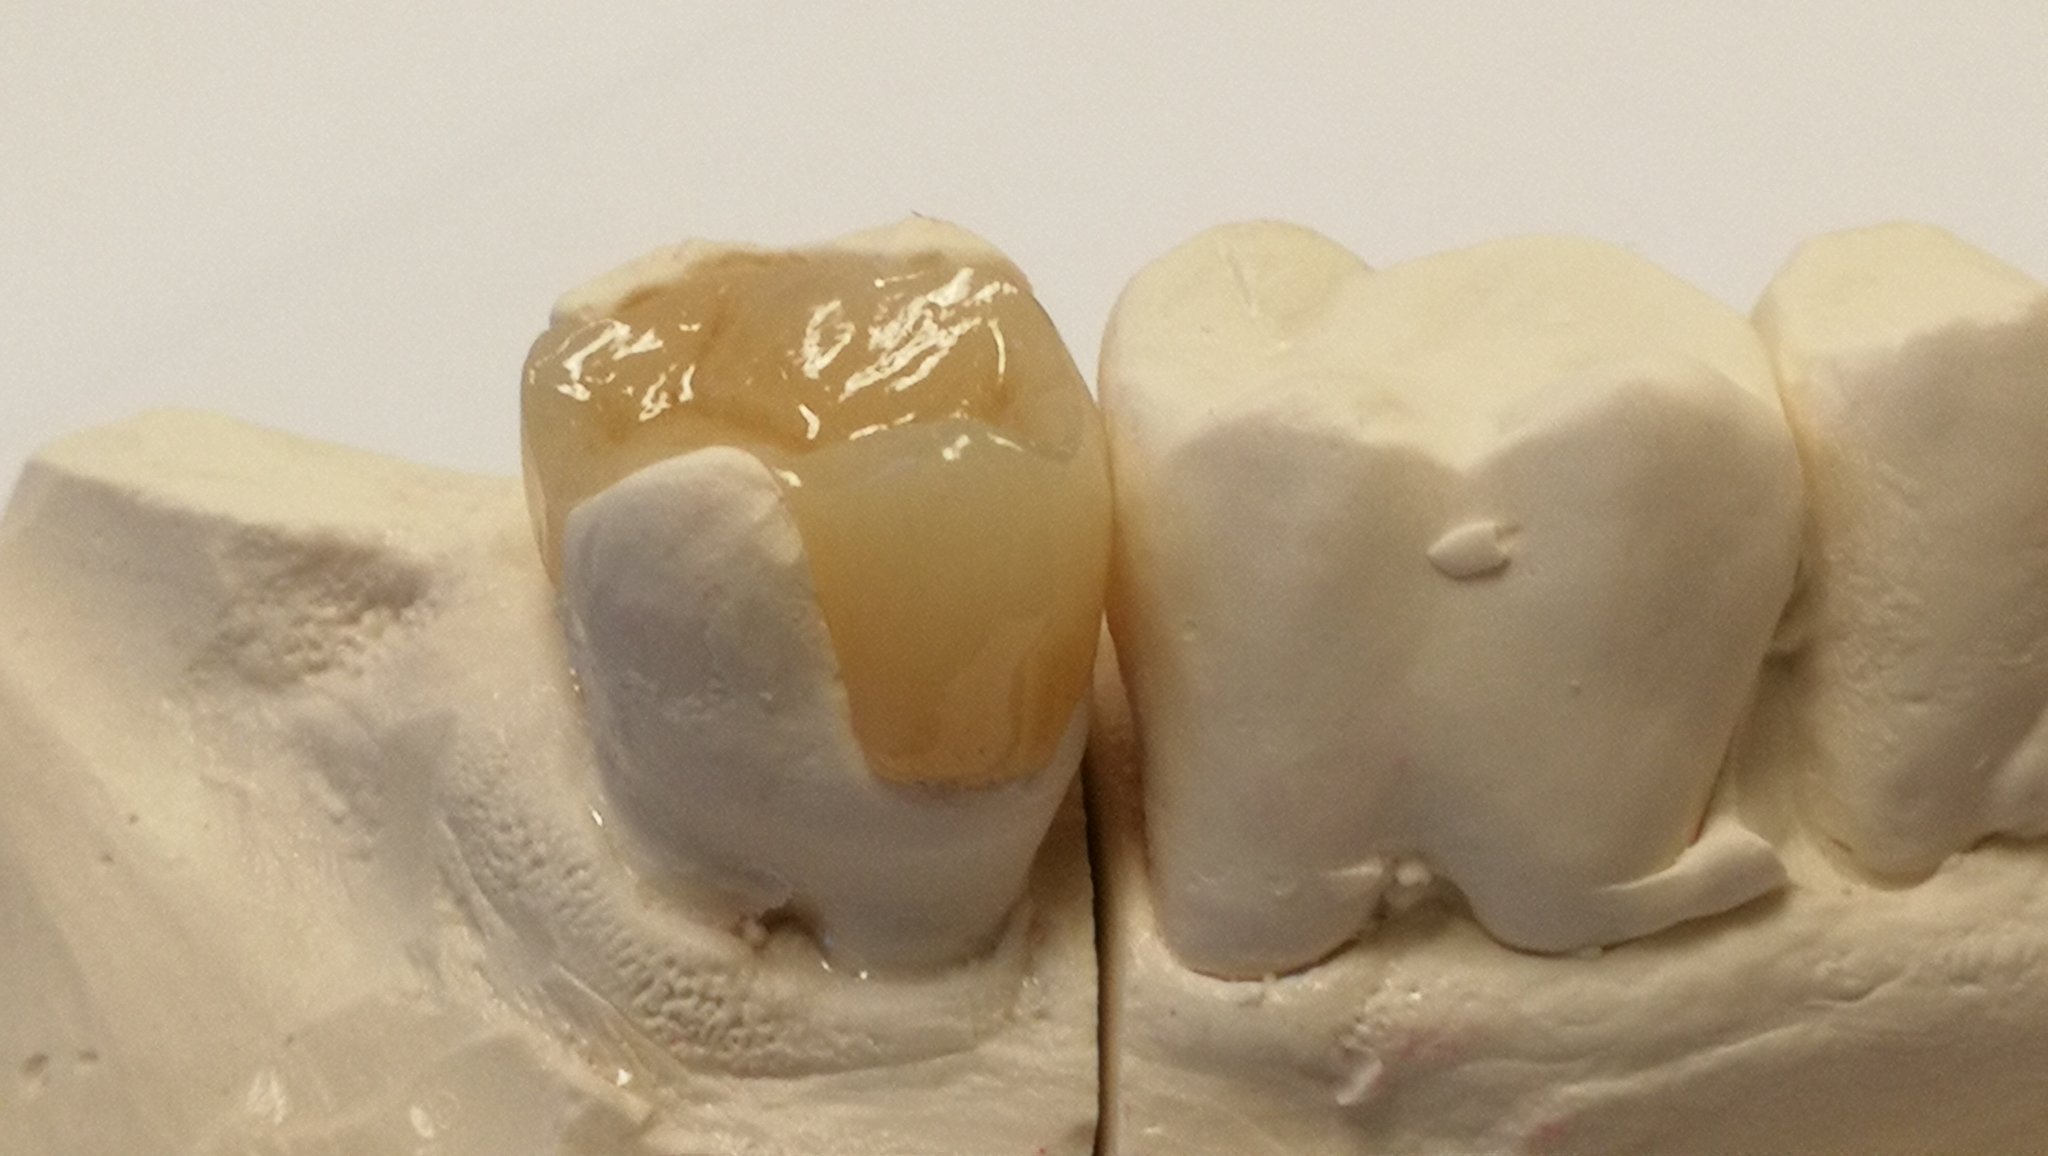

Keramikrestaurationen

Grössere Defekte der Zahnhartsubstanz werden idealerweise in Keramik restauriert. Meist wird das Werkstück von einer Fräsmaschine (CAD; computer-aided

design) aus einem Keramikblock gefräst.

So können grosse Füllungen (Inlay, Onlay, Overlay), Veneers (Verblendschalen) mit höchster Passgenauigkeit und Stabilität hergestellt werden. Nach dem Fräsen wird das Keramikwerkstück mit einem Kompositzement in / auf den Zahn geklebt (einzementiert).